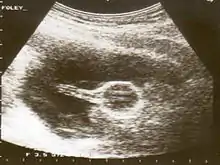

Cervical

A Foley catheter can also be used to ripen the cervix during induction of labor. When used for this purpose, the procedure is called extra-amniotic saline infusion.[8] In this procedure, the balloon is inserted behind the cervical wall and inflated, for example with 30-80 mL of saline.[8] The remaining length of the catheter is pulled slightly taut and taped to the inside of the leg. The inflated balloon applies pressure to the cervix as the baby's head would prior to labor, causing it to dilate. As the cervix dilates over time, the catheter is readjusted to again be slightly taut and retaped to maintain pressure. When the cervix has dilated sufficiently, the catheter drops out.[9]